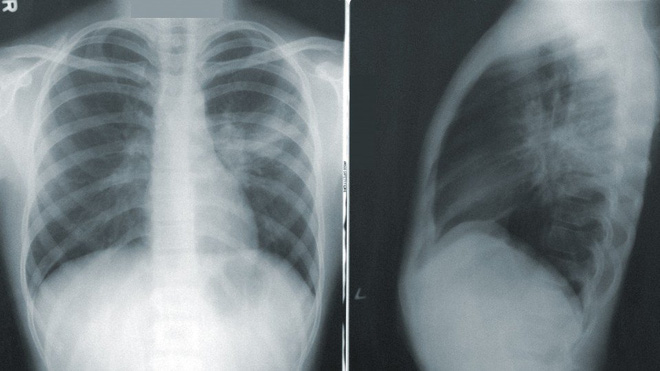

COVID-Net được huấn luyện để phát hiện dấu hiệu bệnh Covid-19 trong hình ảnh chụp x-quang phổi. Cơ sở dữ liệu cho COVID-Net là 5.941 hình ảnh lấy từ 2.839 bệnh nhân với nhiều bệnh phổi khác nhau, từ nhiễm khuẩn, nhiễm virus cho tới nhiễm Covid-19. Bộ dữ liệu này đi kèm luôn với báo cáo khoa học về các khía cạnh kỹ thuật của COVID-Net, để bất kỳ ai có khả năng cũng có thể thử nghiên cứu và góp công xây dựng hệ thống.